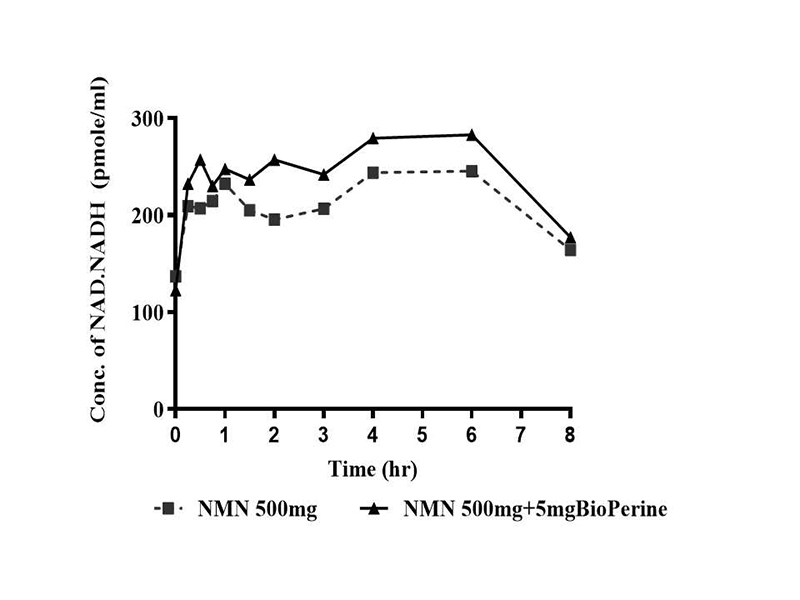

Biểu đồ thể hiện nồng độ trung bình của NAD/NADH ở các nhóm NMN 500mg và NMN 500mg + BioPerine® 5 mg tại các thời điểm khác nhau

Theo biểu đồ minh họa trên, sau khi uống NMN 500 mg, nồng độ NAD/NADH trong máu tăng nhanh, đạt đỉnh trong khoảng 2–4 giờ rồi giảm dần đến giờ thứ 8. Khi kết hợp thêm BioPerine® 5 mg, mức NAD/NADH cao hơn so với chỉ dùng NMN, cho thấy BioPerine có thể cải thiện khả năng hấp thu hoặc duy trì hiệu quả của NMN.